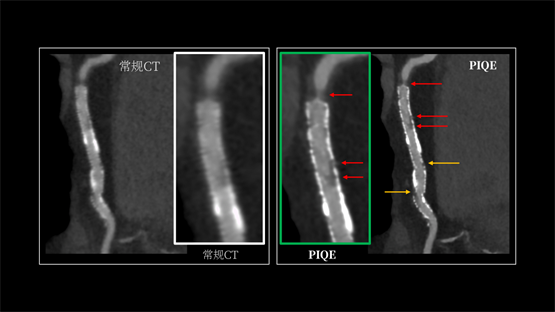

INSIGHT Pioneer利用PIQE技术,首次实现了“16cm宽覆盖 +超高分辨率”在同一CT系统上兼得。它能显著锐化支架轮廓,有效抑制金属伪影与硬化伪影。即便在多枚支架重叠、支架内径细小、严重钙化或心率波动的复杂病例中,依然能清晰显示支架内腔通畅情况及贴壁斑块性质。这意味着,医生在手术规划、介入治疗和术后随访中,都能更可靠地依赖CT来确认结构变化。日本仙台厚生医院心血管内科主任医师Shitaro Honda在实际应用中反馈:“PIQE使直径2.25mm的细小支架也能清晰呈现,能更清晰地显示血管。”

(左图为常规图像,右图为应用PIQE技术后的超高清图像)